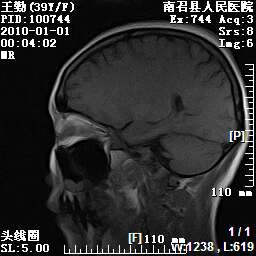

以下是引用随光逐影在2010-1-22 9:03:00的发言:[br]考虑左侧中颅窝(蝶骨翼区)脑膜瘤侵犯蝶骨翼并突入左侧眼眶。

以下是引用水过无痕在2010-1-22 14:55:00的发言:[br]一、定位:颅外占位;二、定性:恶性可能性大;三、组织来源:来源于左侧眼外直肌或其他部位;考虑为:横纹肌肉瘤>转移瘤>脑膜瘤.